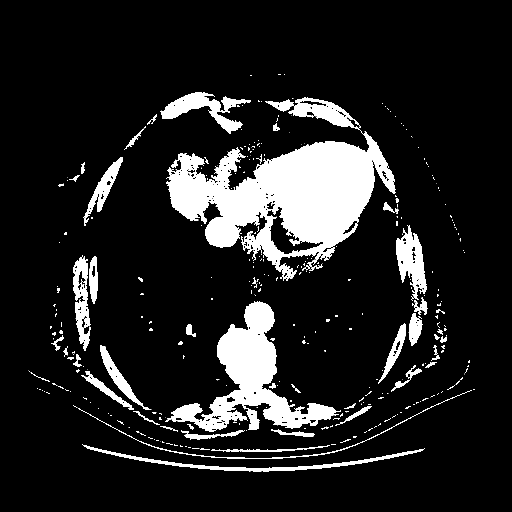

Generated VENOUS CT scan (A→B translation)

Full window (WL 1023.5, WW 4095 β†’ Low βˆ’1024, High +3071)

Actual HU range: [-1024.0, 3071.0]

Lung window (WL -600, WW 1500 β†’ Low βˆ’1350, High +150)

Actual HU range: [-1350.0, 150.0]

Mediastinum window (WL 40, WW 400 β†’ Low βˆ’160, High +240)

Actual HU range: [-160.0, 240.0]